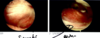

Performed comprehensive diagnostic arthroscopy. I evaluated the gutters for loose body I did not document visualization of the posterior compartment nor the medial meniscus tear. I did characterize the medial meniscal tear of absent any unstable flaps and did not warrant meniscal debridement. I did identify significant stenotic synovitis throughout the joint which underwent a synovectomy I also found a small areas of loose body that was less than 5 mm which I felt was broken up loose bodies. Had significant gapping in the lateral compartment which of poor performance of serial debridements to see if I can retrieve any loose bodies posteriorly however I did not place a trocar into the notch posteriorly to exclude any loose bodies there.

Performed arthroscopic synovectomy using a rotary shaver. In the suprapatellar pouch did not find numerous small loose bodies did not feel criteria to code as a loose body.

The medial compartment I did not identify an abnormal meniscus, I did see unstable cartilage flaps in the medial femoral condyle that elected to perform a chondroplasty using a rotary shaver.